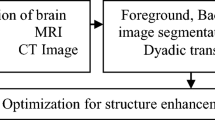

Radiologist diagnose the brain disease through shape and boundary regions of brain in medical image such as CT, MRI, and PET. Automatic medical image segmentation and enhancement method perform less in boundary regions due to artefacts such as dense objects and slice overlap. Manual enhancement and segmentation method never differentiates the shape and location of regions in brain CT/MRI images. Dyadic cat optimization (DCO) algorithm is proposed for segmenting brain regions in medical images such as CT and MRI through Nonlinear perspective Foreground and Background projection. DCO algorithm eliminates the artefacts in the boundary regions of brain and enhances the boundaries and shape such as pterygomaxillary fissure, occipital lobe, vaginal process, zygomatic arch, maxilla and piriform aperture for more visibility. Proposed DCO algorithm enhances the occipital lobe and zygomatic arch regions in CT/MRI image. The occipital lobe and zygomatic arch regions are better enhanced and segmented with DCO algorithm than traditional algorithm and achieve an accuracy of 90% through structural similarity index and visual interpretation.